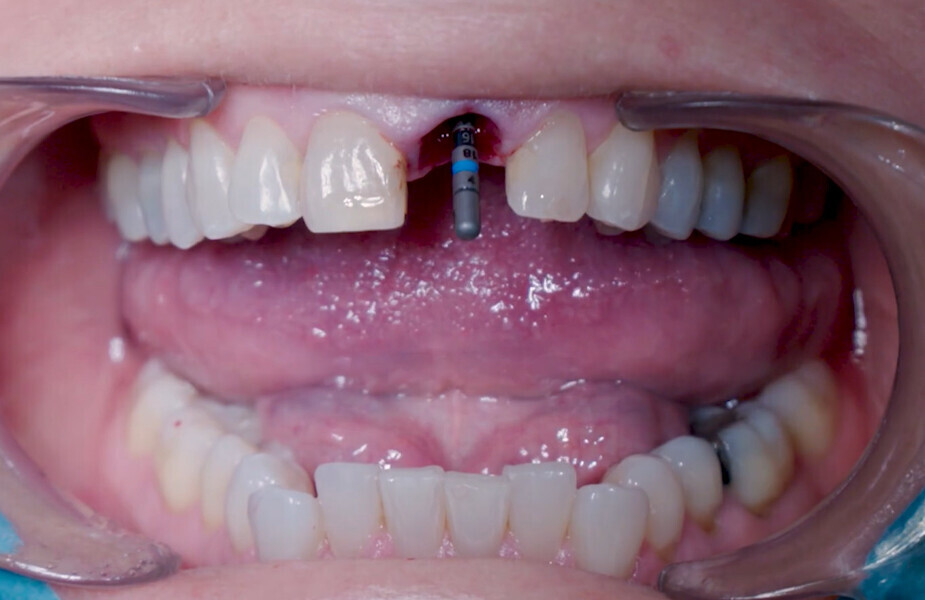

Fig. 12: Final implant position assessment in relation to gingival margins.

Fig. 11: Final implant position assessment.